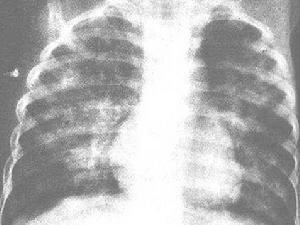

發病緩慢,病程較長,常遷延數月或數年不愈。臨床症狀主要為疲乏、食慾減退、體重減輕及低熱、咳嗽等。初為乾咳,以後有少量白色粘痰,偶帶血絲,咳嗽多於晚間加重,常伴有哮喘發作。肺部可聞乾性囉音,偶有濕性囉音。部分病例出現全身淺表淋巴結輕度腫大及肝臟腫大,在兒童中尤為明顯。偶有脾臟腫大。末梢血液嗜酸性粒細胞明顯增多,血沉增快。約半數病例的血清瓦瑟曼氏反應出現暫時性陽性,血清絲蟲補體結合試驗常呈陽性。肺部 X射線檢查顯示肺紋理增強,有時可見粟粒狀陰影及肺門陰影增寬。診斷時需與過敏性肺炎或勒夫勒氏綜合徵鑑別。砷劑或海群生治療有特效,大劑量左旋咪唑也有效。